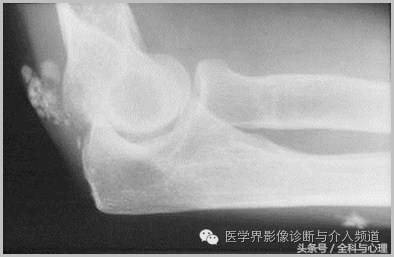

一、肿瘤样钙质沉着症

累及多个关节,范围较大,表现为多房囊状的高密度影。

原发性:罕见,多为家族性,多见于非洲裔美国人,钙磷正常。

继发性:多见于慢性肾功能不全患者。钙磷均有升高。

肿瘤样钙质沉着症